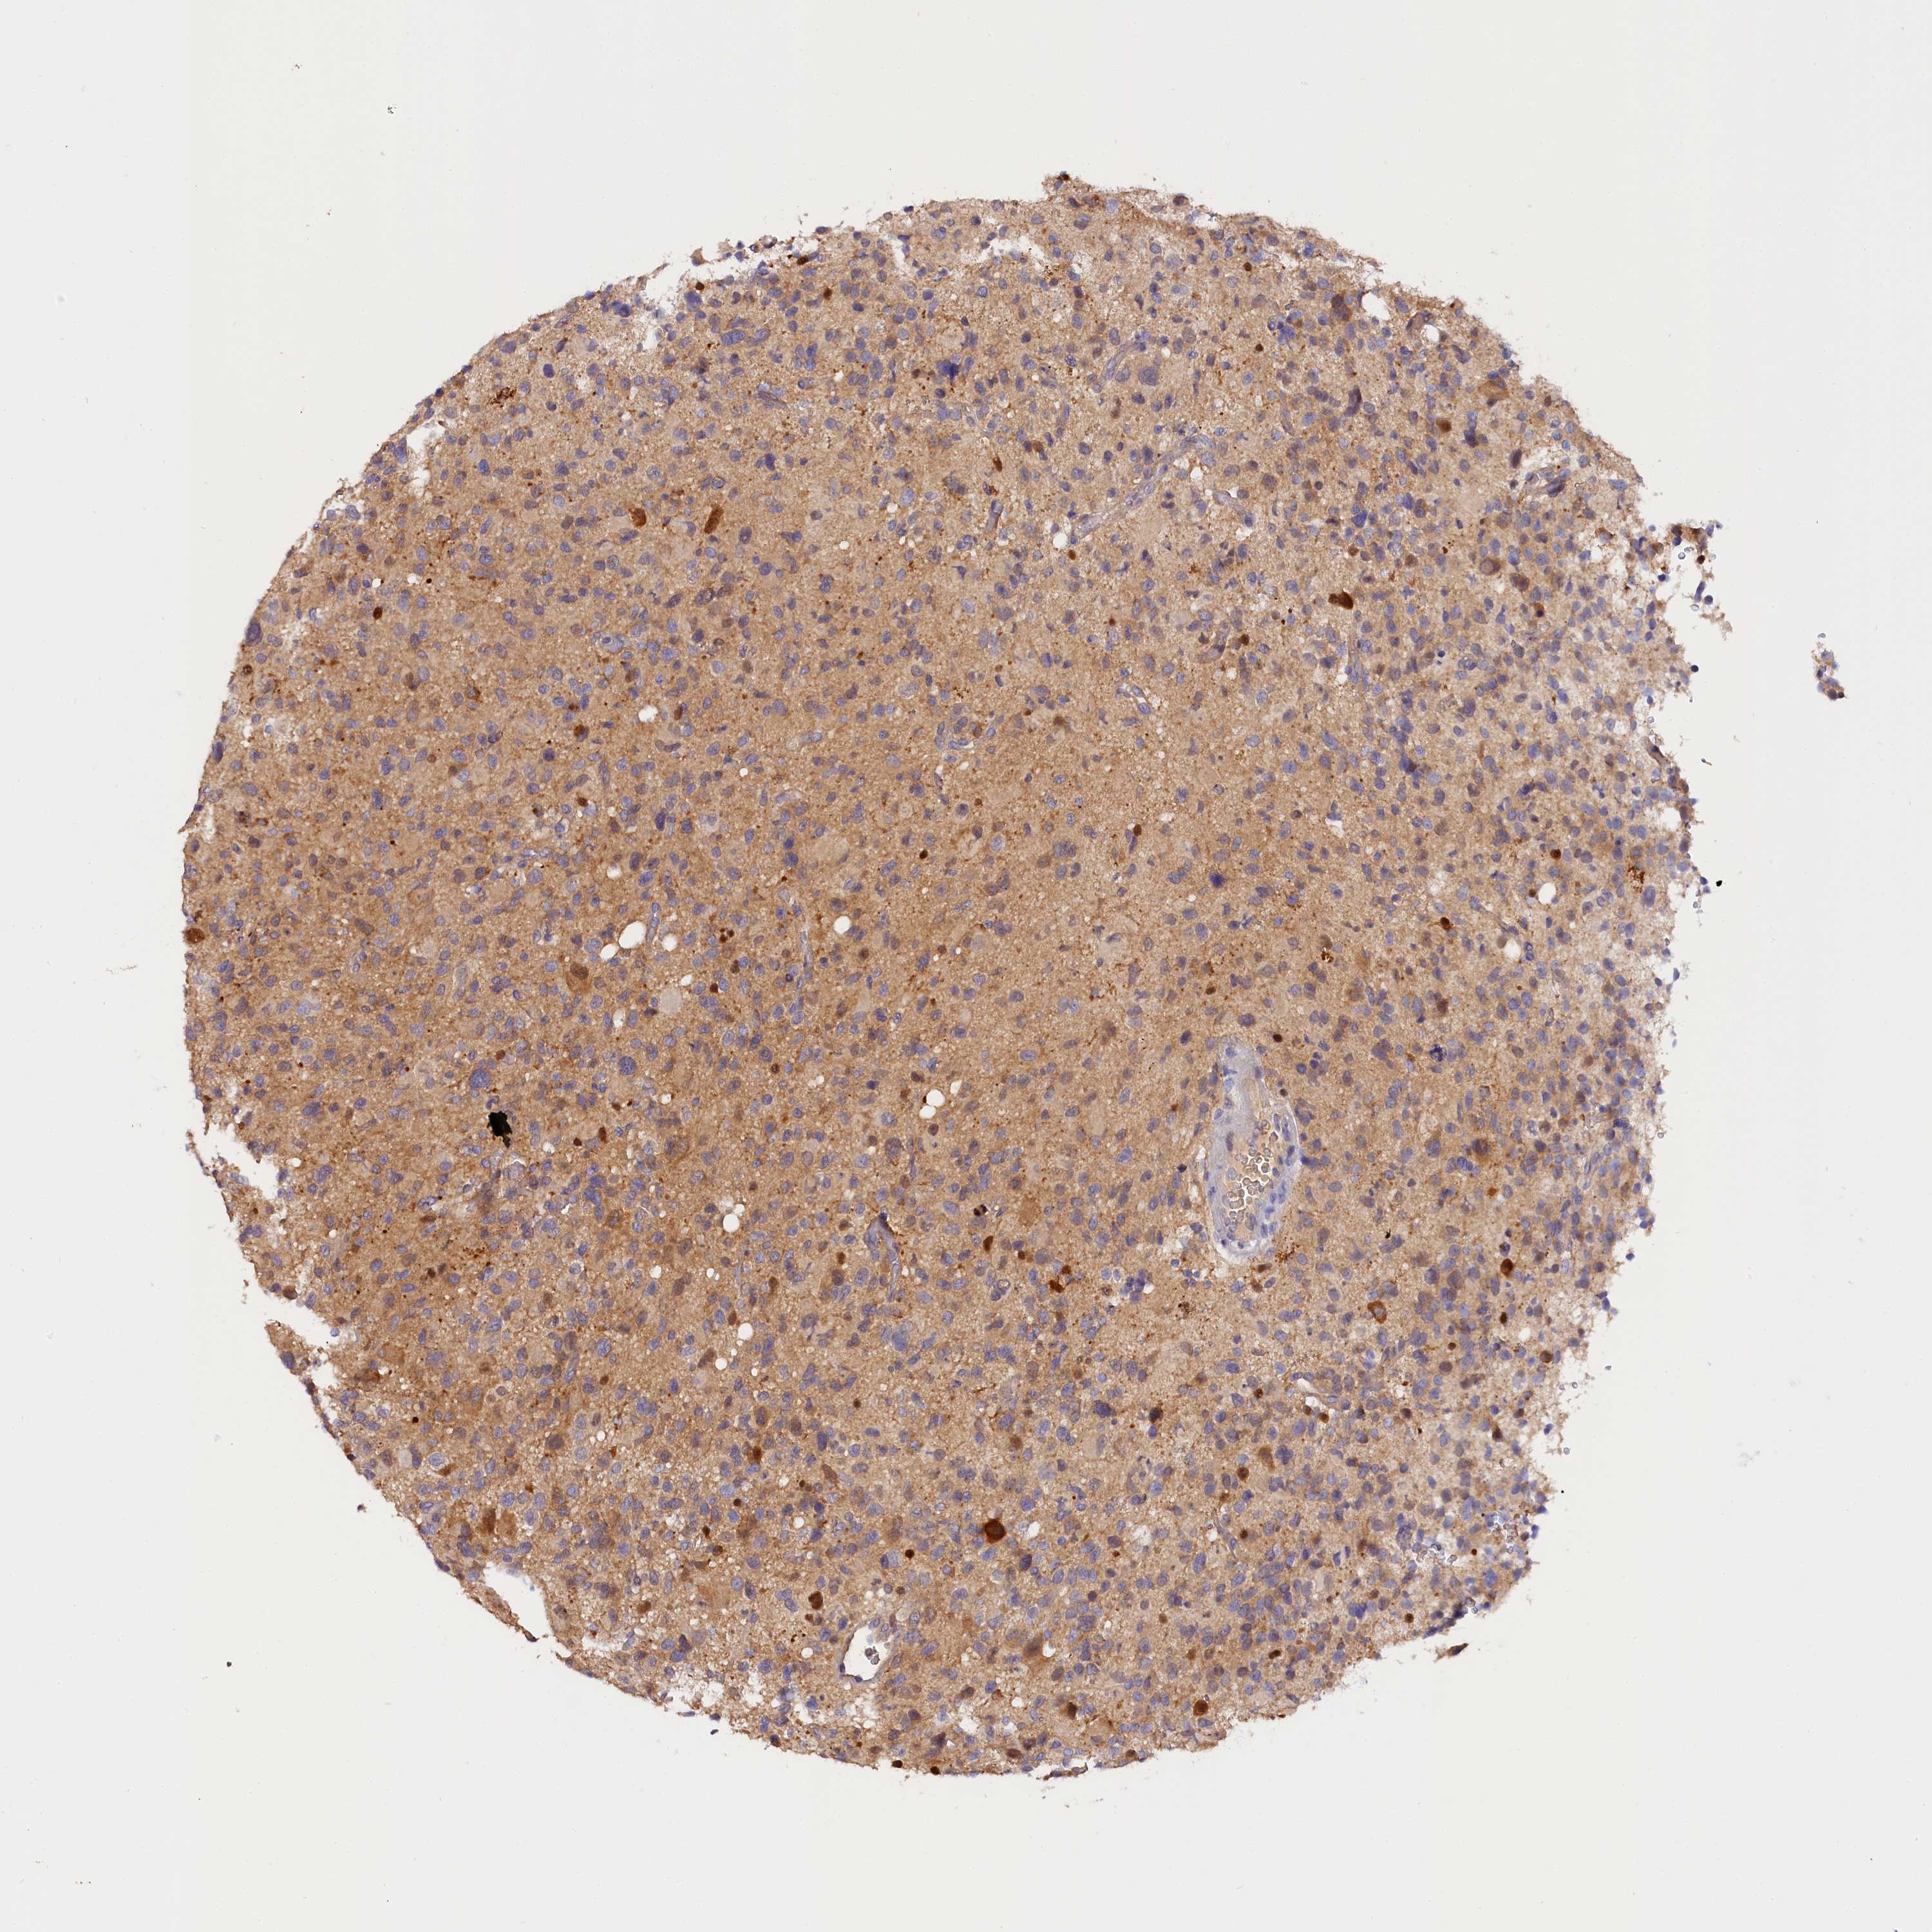

GLIOMA - Protein expressioni

A mouse-over function shows sample information and annotation data. Click on an image to view it in a full screen mode. Samples can be filtered based on level of antibody staining by selecting one or several of the following categories: high, medium, low and not detected. The assay and annotation is described here.

Note that samples used for immunohistochemistry by the Human Protein Atlas do not correspond to samples in the TCGA dataset.

Antibody stainingi

Antibody staining in the annotated cell types in the current human tissue is reported as not detected, low, medium, or high, based on conventional immunohistochemistry profiling in selected tissues. This score is based on the combination of the staining intensity and fraction of stained cells.

Each image is clickable and will lead to virtual microscopy that enables deeper exploration of all samples and also displays staining intensity scores, fraction scores and subcellular localization as well as patient and tissue information for each sample.

Antibody HPA041165

Antibody HPA041839

Staining

High

Medium

Low

Not detected

Intensity

Strong

Moderate

Weak

Negative

Quantity

>75%

75%-25%

<25%

None

Location

Nuclear

Cytoplasmic/membranous

Cytoplasmic/membranous,nuclear

Glioma, malignant, High grade

Glioma, malignant, Low grade